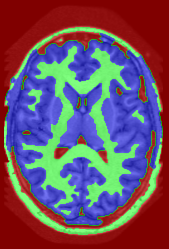

![]() |

|

Subject 3 |

Subject 4 |

| ground truth | a-exp [7, 8] | QPBO [25, 8] | ours | |

Brain Segmentation:

We combined the labeled regions in dataset [19] (T1W MRI) to create the tree shown in Fig. 15(a). In this setting, the data term is the sum of color model penalty and an shape prior [5] based on an automatically extracted brain mask using [16],

where is the intensity at pixel and is the Euclidean Distance Transform of the extracted brain mask. Min-margins are shown in Fig. 15(a). We also added a Hedgehog prior [13] for the sub-cortical grey-matter to help our energy differentiate between grey-matter and sub-cortical grey-matter.

In this application our method outperformed QPBO in most cases and a-exp in all cases. In fact a-exp always converged to a weak local minima in this setting, see Fig. 15. Based on our experience the quality of a-exp result depends on various factors, e.g. tree complexity, the number of min-margins introduced, the order in which labels are expanded, and the initial solution. For the subjects that QPBO was able to find the global optimal Path-Moves either found the global optimal or a very close solution.